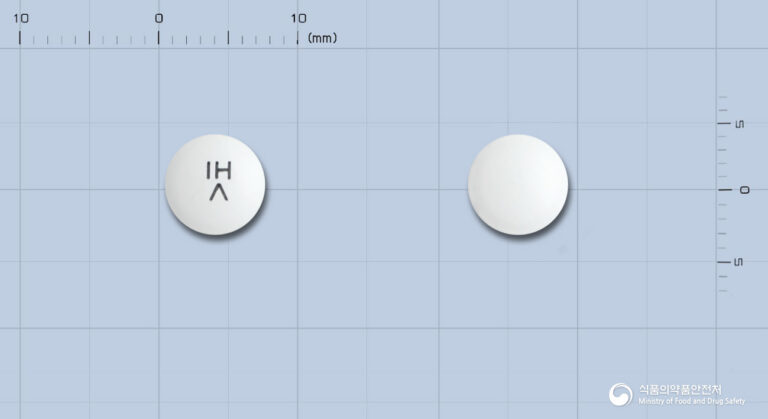

하드칼츄어블이지정: 뼈 건강을 위한 칼슘&비타민 D 보충제

💊 하드칼츄어블이지정 요약 정보 이 약은 식약처 인증 일반의약품입니다. 안녕하세요, 꼼꼼하고 전문적인 약사 블로거입니다. 오늘은 임신ㆍ수유기, 발육기, 노년기에 비타민 D와 칼슘 보급을 돕는 하드칼츄어블이지정에 대해 자세히 알아보겠습니다. 뼈와 이의 발육불량 및 구루병 예방에 사용되는 이 약에 대한 정확한 정보들을 확인하시어 건강 관리에 도움을 받으시길 바랍니다. 1. 효능·효과 임신ㆍ수유기, 발육기, 노년기의 비타민 D 보급 뼈, 이의…